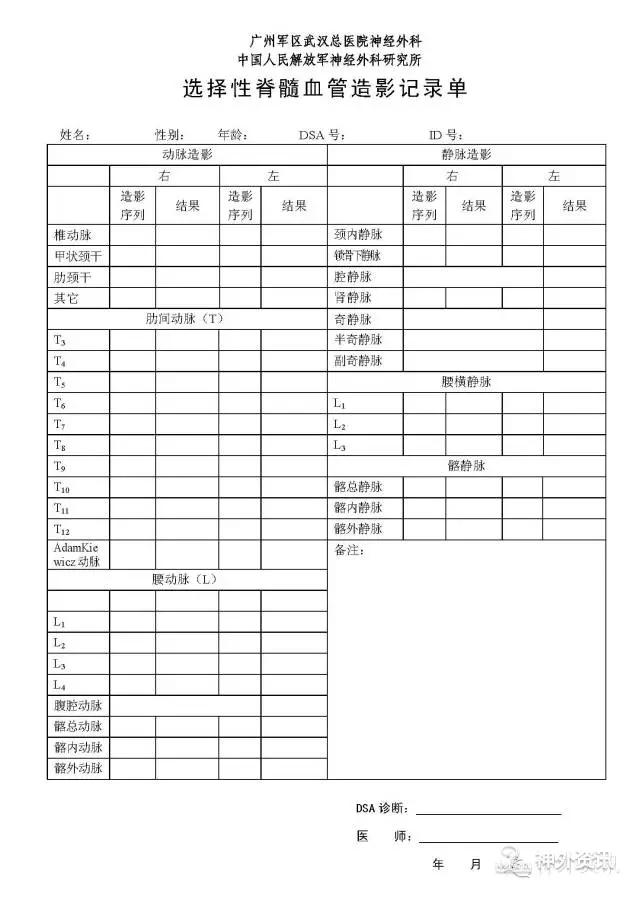

③按我们设计的记录表(表1),记录已完成选择造影血管及结果。

表1. 选择性血管造影记录单。